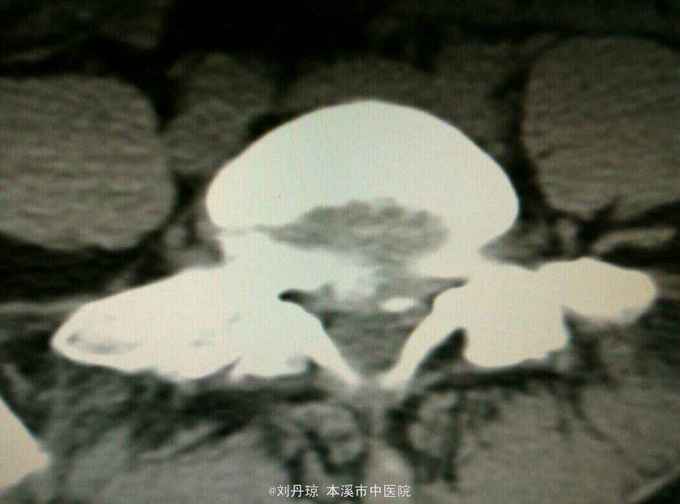

腰部疼痛伴右下肢放射痛麻木感1年,加重1月。患者1年前劳累后感到腰部疼痛伴右下肢放射痛麻木感,近1月病情加重来诊。

查体:L3—S1棘突右旁压痛阳性。直腿抬高实验左70度,右40度。 直腿抬高加强实验左侧阴性,右侧阳性。腰椎功能障碍。 辅查:CT: L3—S1椎间盘突出。